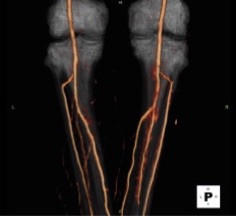

The arterial supply to the peripheral tissues e.g. legs and feet are the most common to be affected by disease and can lead to disabling symptoms. Our CT peripheral angiogram provides exquisitely detailed images of the peripheral arteries to detect narrowing or obstruction to blood flow, with the result and images being reported by a renowned expert in this field.